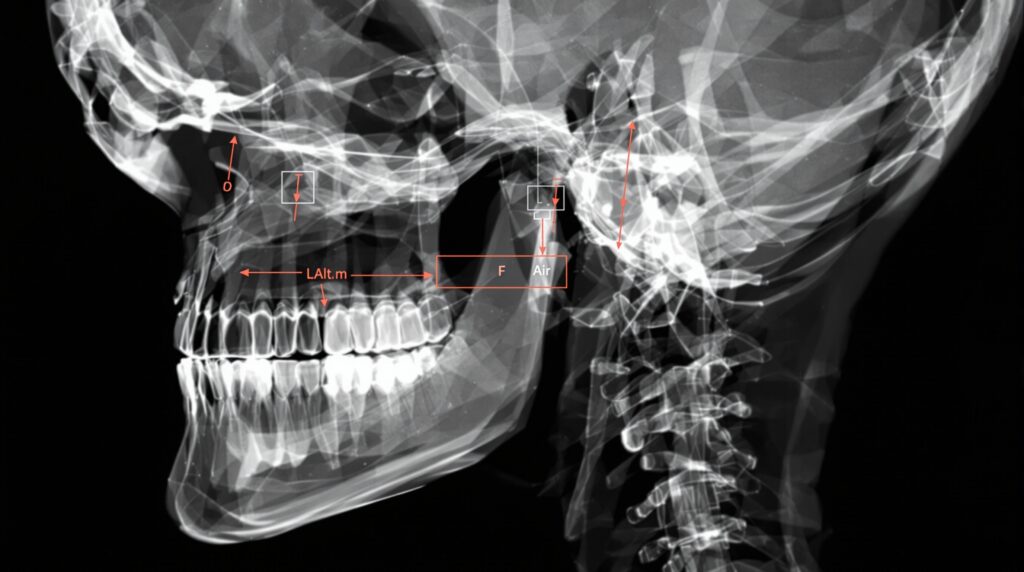

The lateral cephalometric radiograph serves as the primary tool for orthodontic analysis, providing detailed information about anteroposterior and vertical facial relationships. These images allow evaluation of maxillary and mandibular positioning, dental inclinations, and soft tissue profiles. Key anatomical landmarks such as sella, nasion, orbitale, and pogonion form the foundation for comprehensive cephalometric analysis.

Modern cephalometric analysis relies on established protocols such as the Steiner analysis and Downs analysis, which provide normative values for various angular and linear measurements. These standardized approaches help orthodontists determine skeletal classification, evaluate growth patterns, and develop appropriate treatment strategies for individual patients.